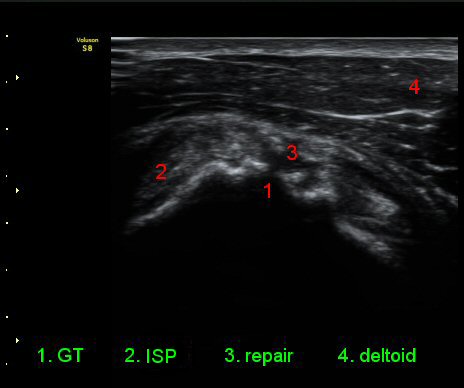

ŽÃÊÀÚ¸¦ ¾à°£ ´Ù¸®ÂÊ, ³»ÃøÀ¸·Î À̵¿ÇÏ´Ï °ß°©ÇÏ±Ù°Ç Ç¥Ãþ¿¡ ¸¹Àº ¾çÀÇ ¼ö¾×Àú·ù°¡ °üÂûµÈ´Ù(»çÁø 3).

¾î±ú¸¦ ³»Àü, ³»È¸Àü, ½ÅÀüÇÏ¿© ±Ø»ó°Ç°Ë»ç¿¡¼­ ±Ø»ó°Ç ÆÄ¿­ ÈÄ ¼ö¼úÇÑ ¼Ò°ß, ±Ø»ó°ÇÀÇ

Àú¿¡ÄÚ ºÎÁ¾°ú ºÎºÐÀû ÆÄ¿­, °í¿¡ÄÚ ºÀÇÕ»ç, ´ë°áÀýÀÇ ºÒ±ÔÄ¢º¯È­,À» º¸¿©ÁØ´Ù(»çÁø 6, 7, 8, 9)